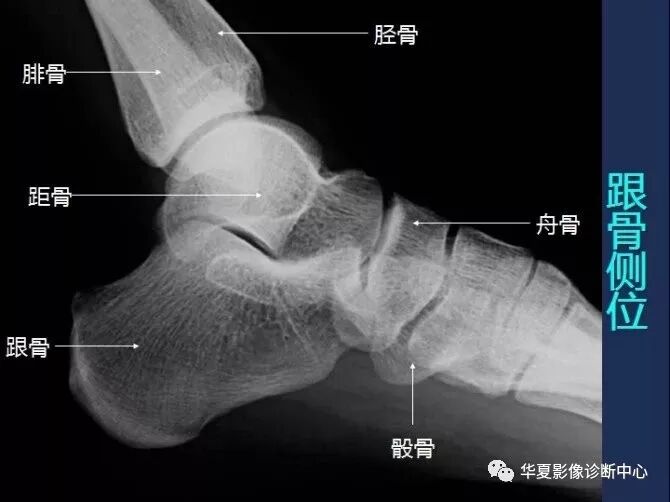

【工作必备】X线解剖图谱+系统解剖(骨骼篇),非常全面,强烈建议收藏~